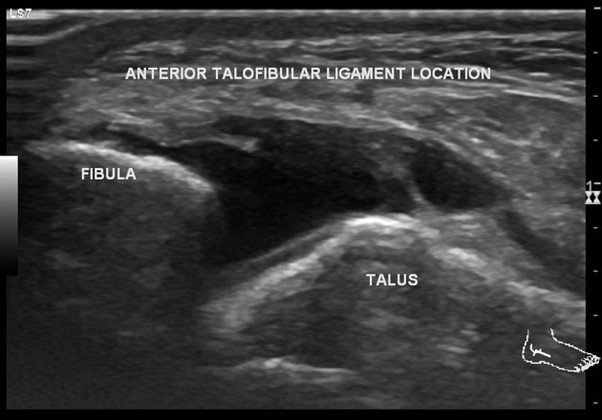

Ultrasound scan showing Anterior Talofibular ligament( ATFL) injury

- Diagnostic Ultrasound: Useful for identifying bursitis, tendonitis, and ligament injuries in real-time.

- The lateral ligament complex includes three primary ligaments: anterior talofibular ligament (ATFL), calcaneofibular ligament (CFL), and posterior talofibular ligament (PTFL). These ligaments stabilize the outer side of the ankle.

- Most injuries occur due to an inversion injury, where the ankle rolls outward, causing tearing or overstretching of the ligaments. Symptoms include swelling, bruising, and pain on the outer side of the ankle.